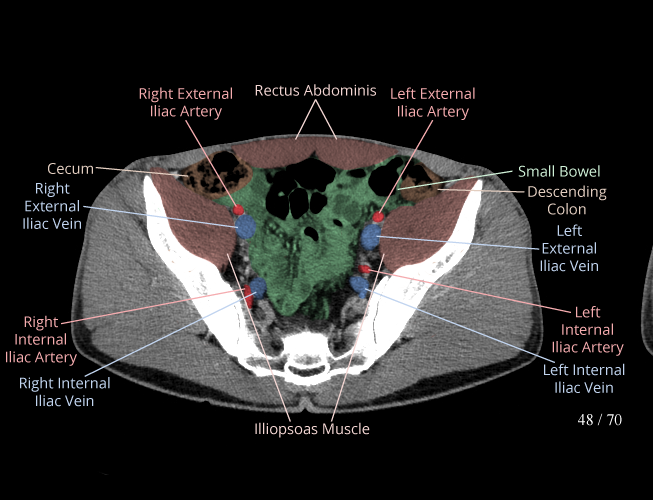

Body

Covers abdominal CT anatomy.

Pelvis

Covers pelvic MRI anatomy.